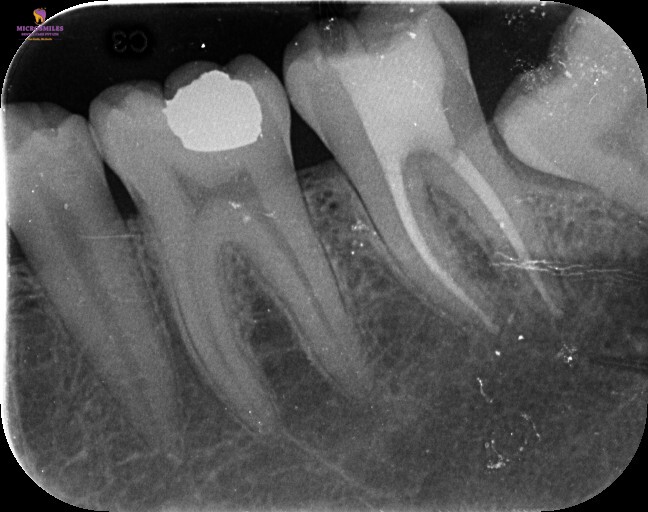

At Microsmiles, every root canal is performed under a high-resolution dental microscope, allowing our specialists to treat even the most complex canals with pinpoint accuracy. This level of detail isn’t just high-tech-it leads to faster treatment, fewer appointments, and long-lasting results.

By detecting and treating even the smallest problems early, we help you avoid bigger issue down the line-reducing the chances of complications or costly future treatments.